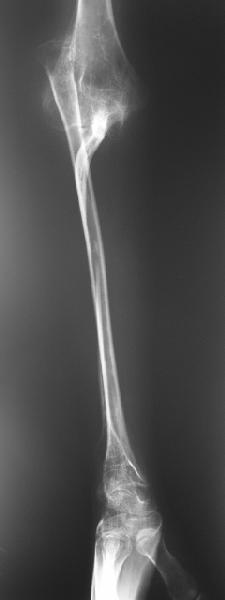

Молодой человек 2-3 года назад наблюдался по поводу прогрессирующего остеолиза правой локтевой кости. Морфологически - гемангиома, возможно, ангиомоподобный остеолиз (болезнь Gorham-Stout). Получал лучевую терапию. К настоящему времени остеолиз не прогрессирует. Однако сформировался вывих лучевой кости. Рентгенограмма и функция - см. иллюстрации. Пациенту хотелось бы улучшить функцию. Что можно предложить? Постепенное вправление аппаратом, замещение дефекта локтевой кости, резекцию головки лучевой, оставить как есть, что-то еще?

Судя по рентгенограмме, сформировался плечелоктевой артродез под углом около 90 градусов, поэтому тот объем движений, который выполняет пациент, обеспечивается за счет дефекта локтевой кости.